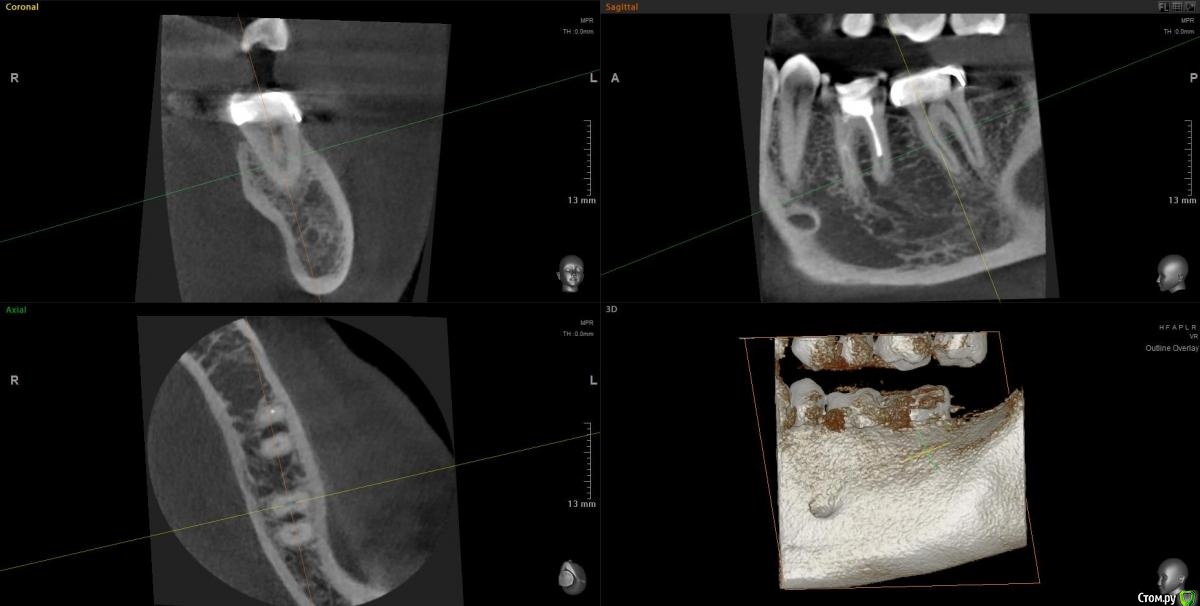

Slava76 Опубликовано 7 декабря, 2020 Автор Поделиться Опубликовано 7 декабря, 2020 (изменено) Сегодня сделал КТ. Выложил здесь https://cloud.mail.ru/public/2ezX/2HwT6HocyНа вечер записался к другому врачу. Послушаю, что он скажет.До обеда при нажатие была небольшая боль. Сейчас практически ее не чувствую. И так уже 4 дня. P.s.1 очень боюсь начать лечить не тот зуб. Коронку очень не хочется трогать. Ей все два года. Делала ее очень хороший врач.P.s.2 может само все пройдет... Изменено 7 декабря, 2020 пользователем Slava76 Ссылка на комментарий

Slava76 Опубликовано 7 декабря, 2020 Автор Поделиться Опубликовано 7 декабря, 2020 Вернулся от врача. Он посмотрел КТ и подтвердил слова DmitrySH. На 90% врач уверен, что проблема из-за не до конца залеченного канала и сломанного инструмента. Сказал, что нужно лечение под микроскопом. У них в поликлинике таких специалистов нет. Завтра начну искать такого врача в Нижнем Ссылка на комментарий

wladdX Опубликовано 7 декабря, 2020 Поделиться Опубликовано 7 декабря, 2020 (изменено) Трещины в зубе 37 не увидел Изменено 7 декабря, 2020 пользователем wladdX Ссылка на комментарий

Slava76 Опубликовано 8 декабря, 2020 Автор Поделиться Опубликовано 8 декабря, 2020 (изменено) Трещины в зубе 37 не увидел Значит однозначно "виноват" зуб с пломбой. Буду перелечивать каналы (если найду, кто вытащит сломанный инструмент) и ставить коронку.Звонил сейчас в одну из клиник, говорят вместо микроскопа используют специальные очки. С ними реально вытащить сломавшийся инструмент? Изменено 8 декабря, 2020 пользователем Slava76 Ссылка на комментарий